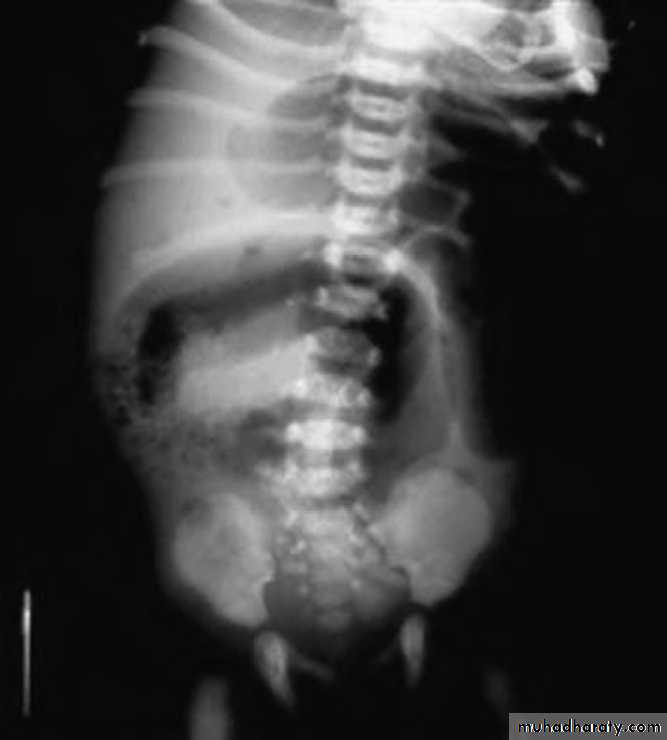

4-Meconium Plug Syndrome

Present with the same triad of intestinal obstruction :

1.Abdominal distension .

2.Vomiting

3.Delayed passage of meconium.

This is due to inspissated plug of meconium at the distal end the meconium column in the rectum .

• investigation:

• 1.Plain X-ray is normal in the early stage ,fluid levels occur at the late stage .

• 2. Contrast study is normal and can relieve the obstruction.